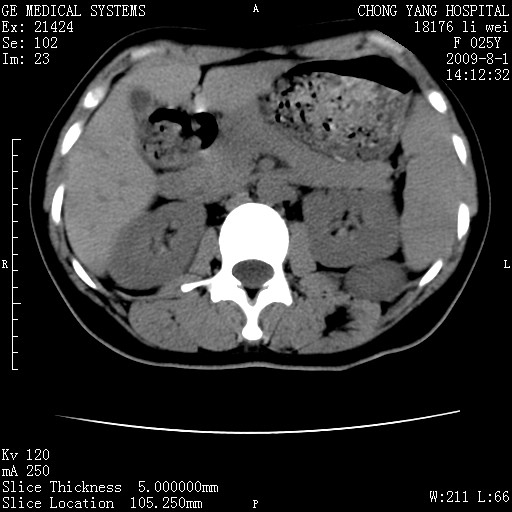

以下是引用拾荒者在2009-12-30 21:45:00的发言:[br]ct21383:神经纤维瘤病( nf) [br] [br] 神经纤维瘤病。四肢都有,影响美观,四肢上的手术了。[br] [br] [br]谢谢!